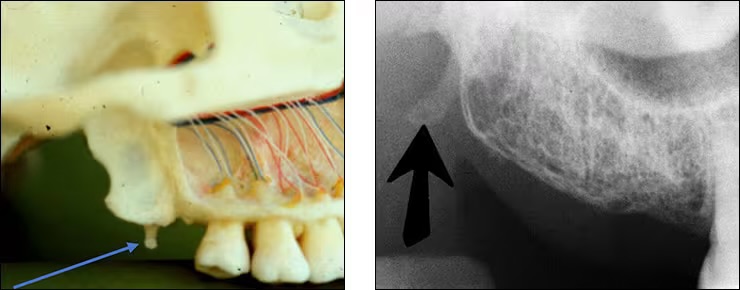

Lingual foramen

Small pinpoint opening in bone on the lingual aspect of anterior mandible.

Surrounded by genial tubercle.

(for lingual nerve and arteries)

Genial tubercles

aka mental spine

Spiny protuberance (sometimes 2) of bone located in the midline on the lingual aspect of mandible below roots of incisor teeth